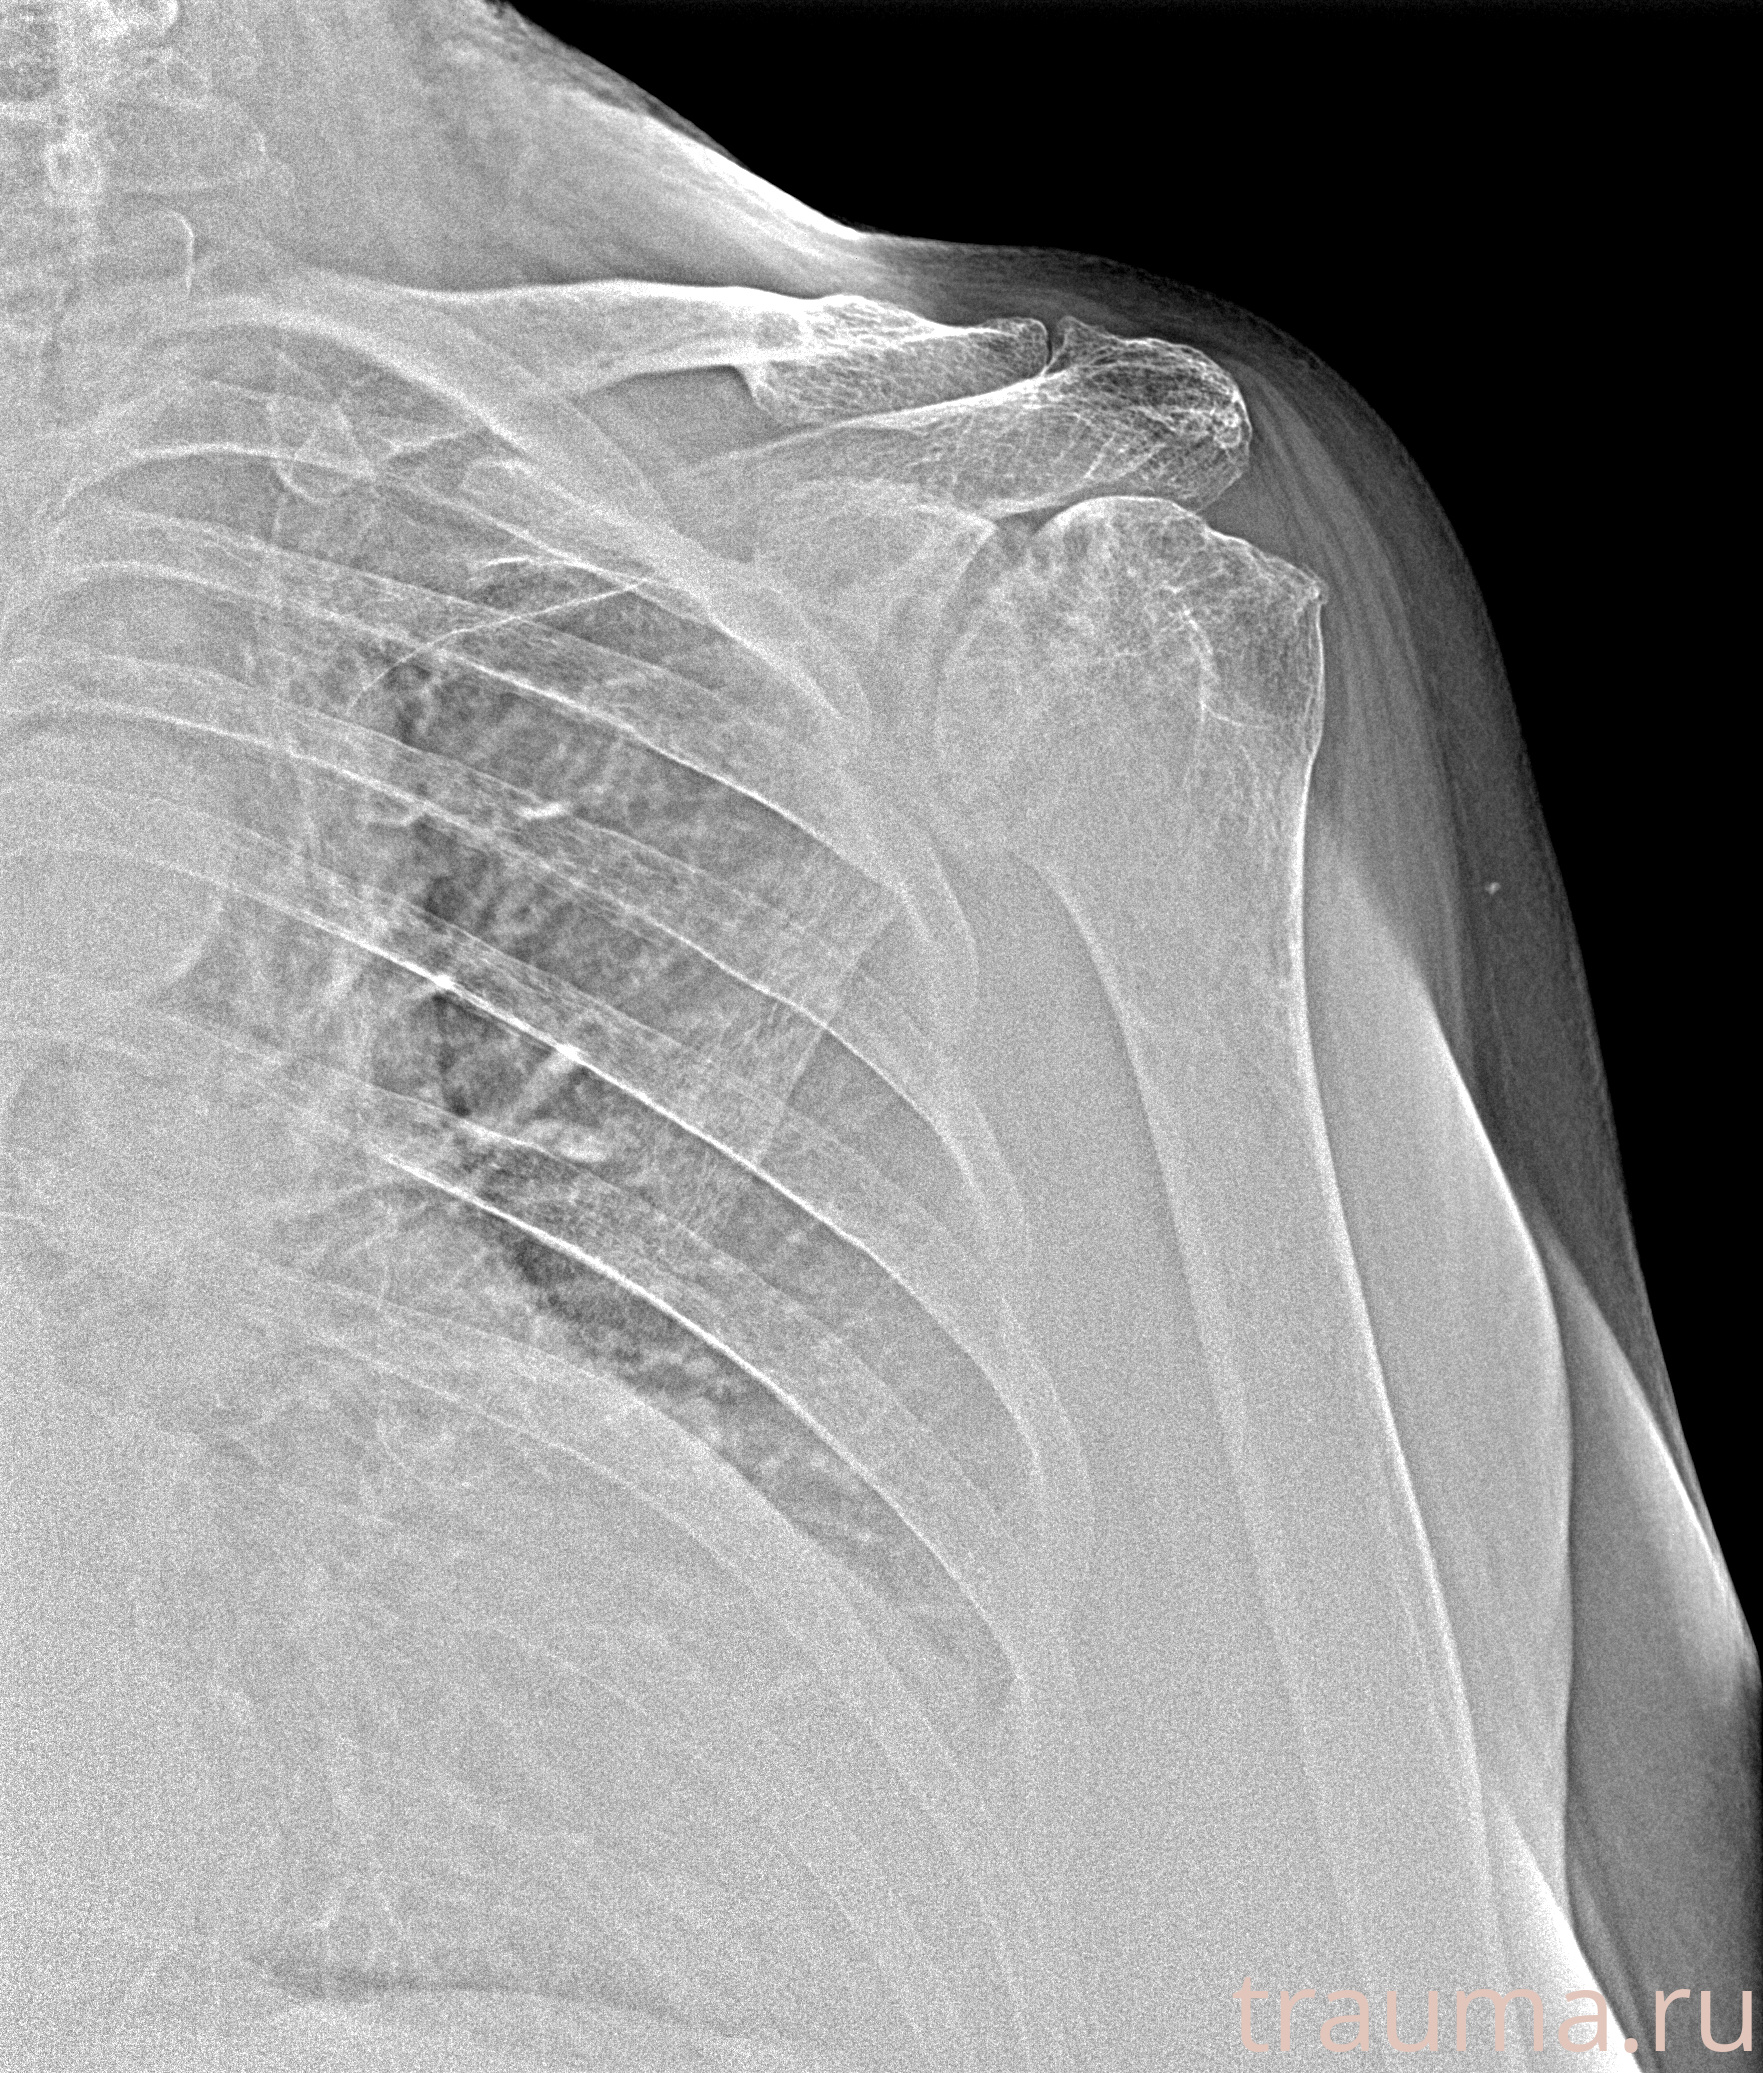

Рентгенограммы

Рентген на дому: по вашему адресу приезжает врач-рентгенолог, травматолог-ортопед с мобильным рентгеновским аппаратом, проводит диагностику травмы или заболевания, делает необходимые рентгенограммы, дает рекомендации по дальнейшему лечению. Получить качественные снимки в домашних условиях возможно благодаря уникальной методике, разработанной МосРентген Центром для института  Склифосовского